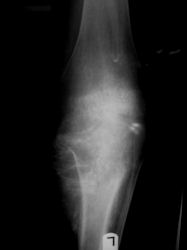

Radiographic imaging is used to help form a diagnosis. These include X-Ray, MRI, CT and Bone Scans.

An example of a Conventional Osteosarcoma X-Ray is shown.